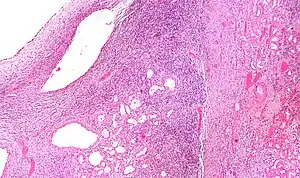

| Micrograph of a cystic nephroma (left of image). Normal kidney is seen on the right. H&E stain. | |

Micrograph of a cystic nephroma. H&E stain.